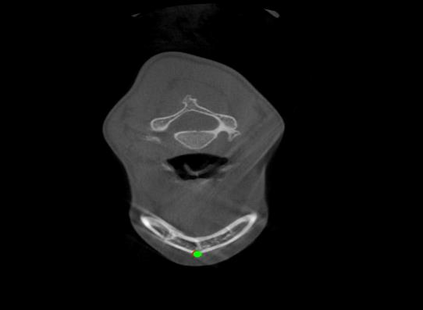

Detecting 3D landmarks on cone-beam computed tomography (CBCT) is crucial to assessing and quantifying the anatomical abnormalities in 3D cephalometric analysis. However, the current methods are time-consuming and suffer from large biases in landmark localization, leading to unreliable diagnosis results. In this work, we propose a novel Structure-Aware Long Short-Term Memory framework (SA-LSTM) for efficient and accurate 3D landmark detection. To reduce the computational burden, SA-LSTM is designed in two stages. It first locates the coarse landmarks via heatmap regression on a down-sampled CBCT volume and then progressively refines landmarks by attentive offset regression using multi-resolution cropped patches. To boost accuracy, SA-LSTM captures global-local dependence among the cropping patches via self-attention. Specifically, a novel graph attention module implicitly encodes the landmark's global structure to rationalize the predicted position. Moreover, a novel attention-gated module recursively filters irrelevant local features and maintains high-confident local predictions for aggregating the final result. Experiments conducted on an in-house dataset and a public dataset show that our method outperforms state-of-the-art methods, achieving 1.64 mm and 2.37 mm average errors, respectively. Furthermore, our method is very efficient, taking only 0.5 seconds for inferring the whole CBCT volume of resolution 768$\times$768$\times$576.